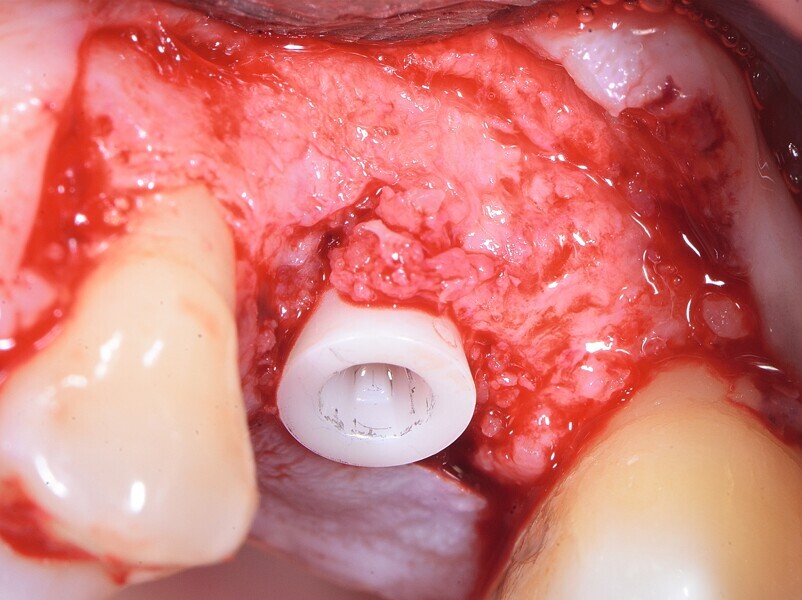

Fig. 8 : Fin du traitement chirurgical. Implant deux pièces en céramique au niveau tissulaire.

Fig. 9 : Fin du traitement chirurgical. Implant deux pièces en céramique au niveau tissulaire.

Fig.10 : Fin du traitement chirurgical. Implant deux pièces en céramique au niveau tissulaire.

La première phase du traitement implantaire a consisté à extraire la dent et à préserver l’alvéole au moyen d’une allogreffe et d’une membrane de collagène. Six mois après, l’os régénéré a permis de procéder à la seconde phase du traitement comportant la pose d’un implant deux pièces en céramique (Figs. 1–11).